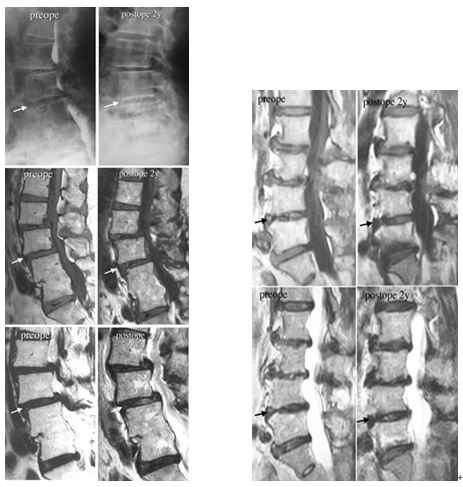

再以椎间盘退化为例。一篇案例报道显示[2]:两例腰椎间盘明显退化的患者接受了含有自体间充质干细胞的胶原海绵片移植,2年后,CT和MRI显示两名患者的退化椎间盘得到修复,椎间真空现象有所改善,在T2加权MRI上,与手术前相比,椎间盘的信号强度增高,表明水分含量增高。手术后症状也得到缓解,腰背痛,小腿麻木,疼痛等症状显著减轻。

图片来自文献[2]